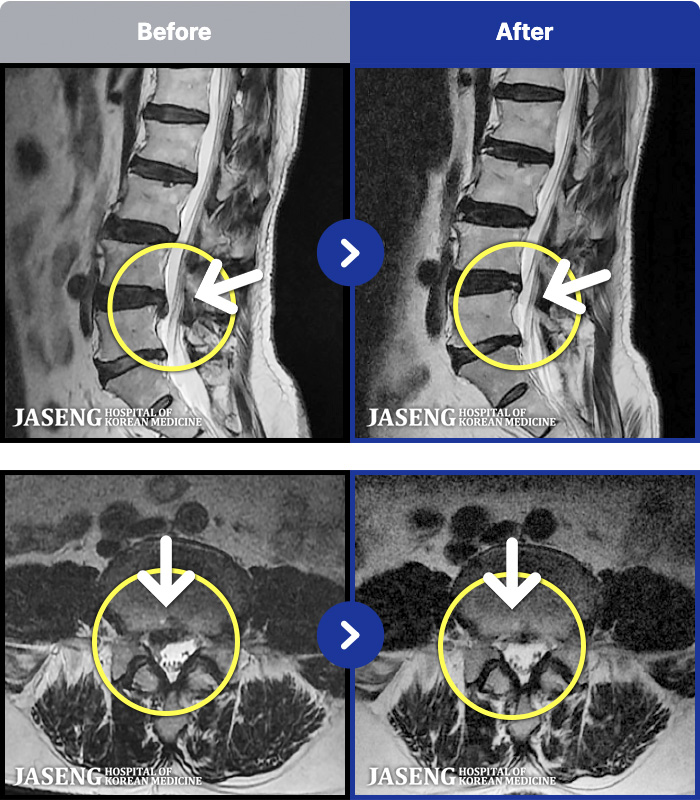

MRI ġ

129 MRI ũ ʸ Ȯϼ.